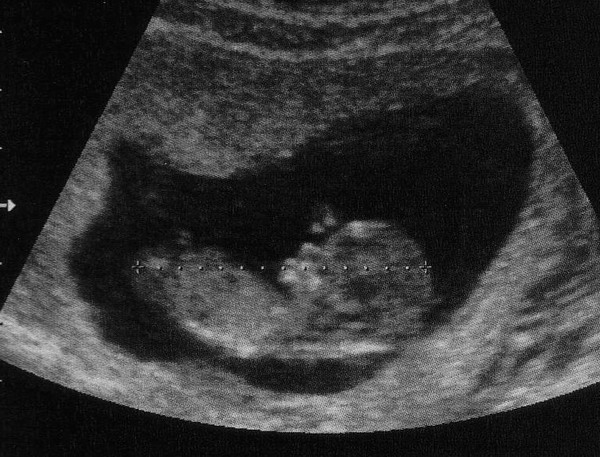

tarkóredő :0,9 és a baba most 5 centis :)

Prüntyi, már 5 centi :) :) :)! és ficánkolt? :)